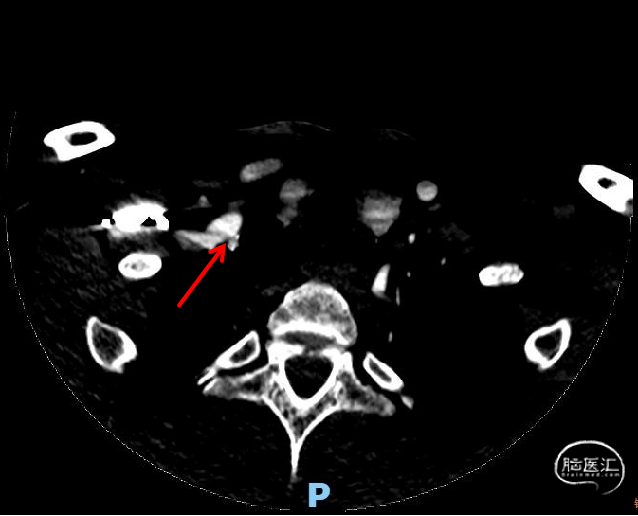

术前头颈部CTA示:(1)左侧锁骨下动脉、左颈总动脉、右锁骨下动脉起始部、双侧颈内动脉粥样硬化表现。(2)右侧椎动脉起始部粥样硬化表现,管腔中-重度狭窄。